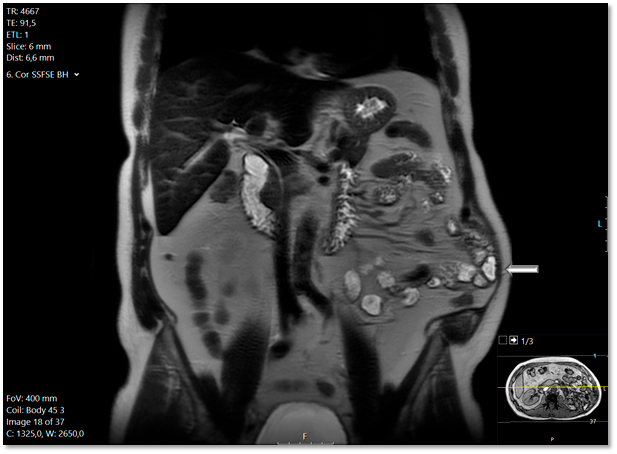

Die Narbenhernie wurde von dem Radiologen erst elf Monate nach der Nephrektomie diagnostiziert. Der Radiologe räumte nunmehr in seinem Befundbericht ein, dass diese sich auch schon in der Voruntersuchung andeutete – siehe Abbildung 1. Sie wurde einen Monat später laparoskopisch mit Einbringung eines Netzes versorgt. Postoperativ gab der Patient weiter erhebliche Beschwerden an: „im Stehen deutliche Vorwölbung linke Flanke/laterale Bauchwand, im Stehen und Liegen keine Bruchpforte tastbar. Befund auch wie bei Relaxatio der Bauchwand.“ Es folgten zahlreiche Konsultationen bei verschiedensten Chirurgen und Neurologen – allesamt nicht mit dem gewünschten Erfolg aus Sicht des Patienten.

Der „fehlende Befund“ ist in der Bildgebung 1 vorhanden, wird jedoch eben nicht kommuniziert und damit übersehen. Dies stellt mit 42 % die höchste Fehlerklassifikation in der diagnostischen Radiologie dar.1